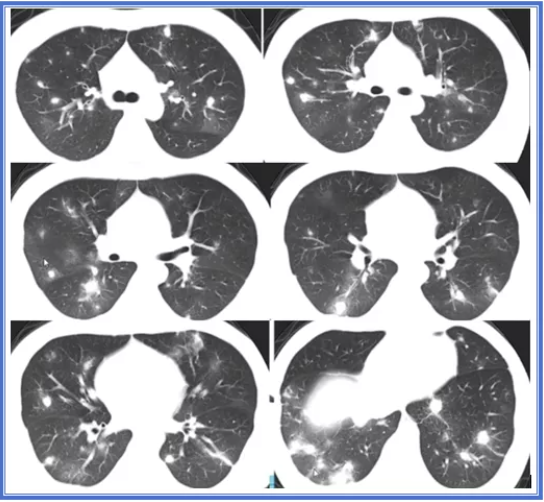

2、气道侵袭型肺曲霉病的HRCT表现

树芽征

骨髓移植术后,发热、咳嗽

免疫正常患者常见影像 1、气道播散性肺曲霉病(常见于有气道疾病背景者)

细支气管炎或支气管炎;树芽征;非对称团片影或/和双侧向心性实变。